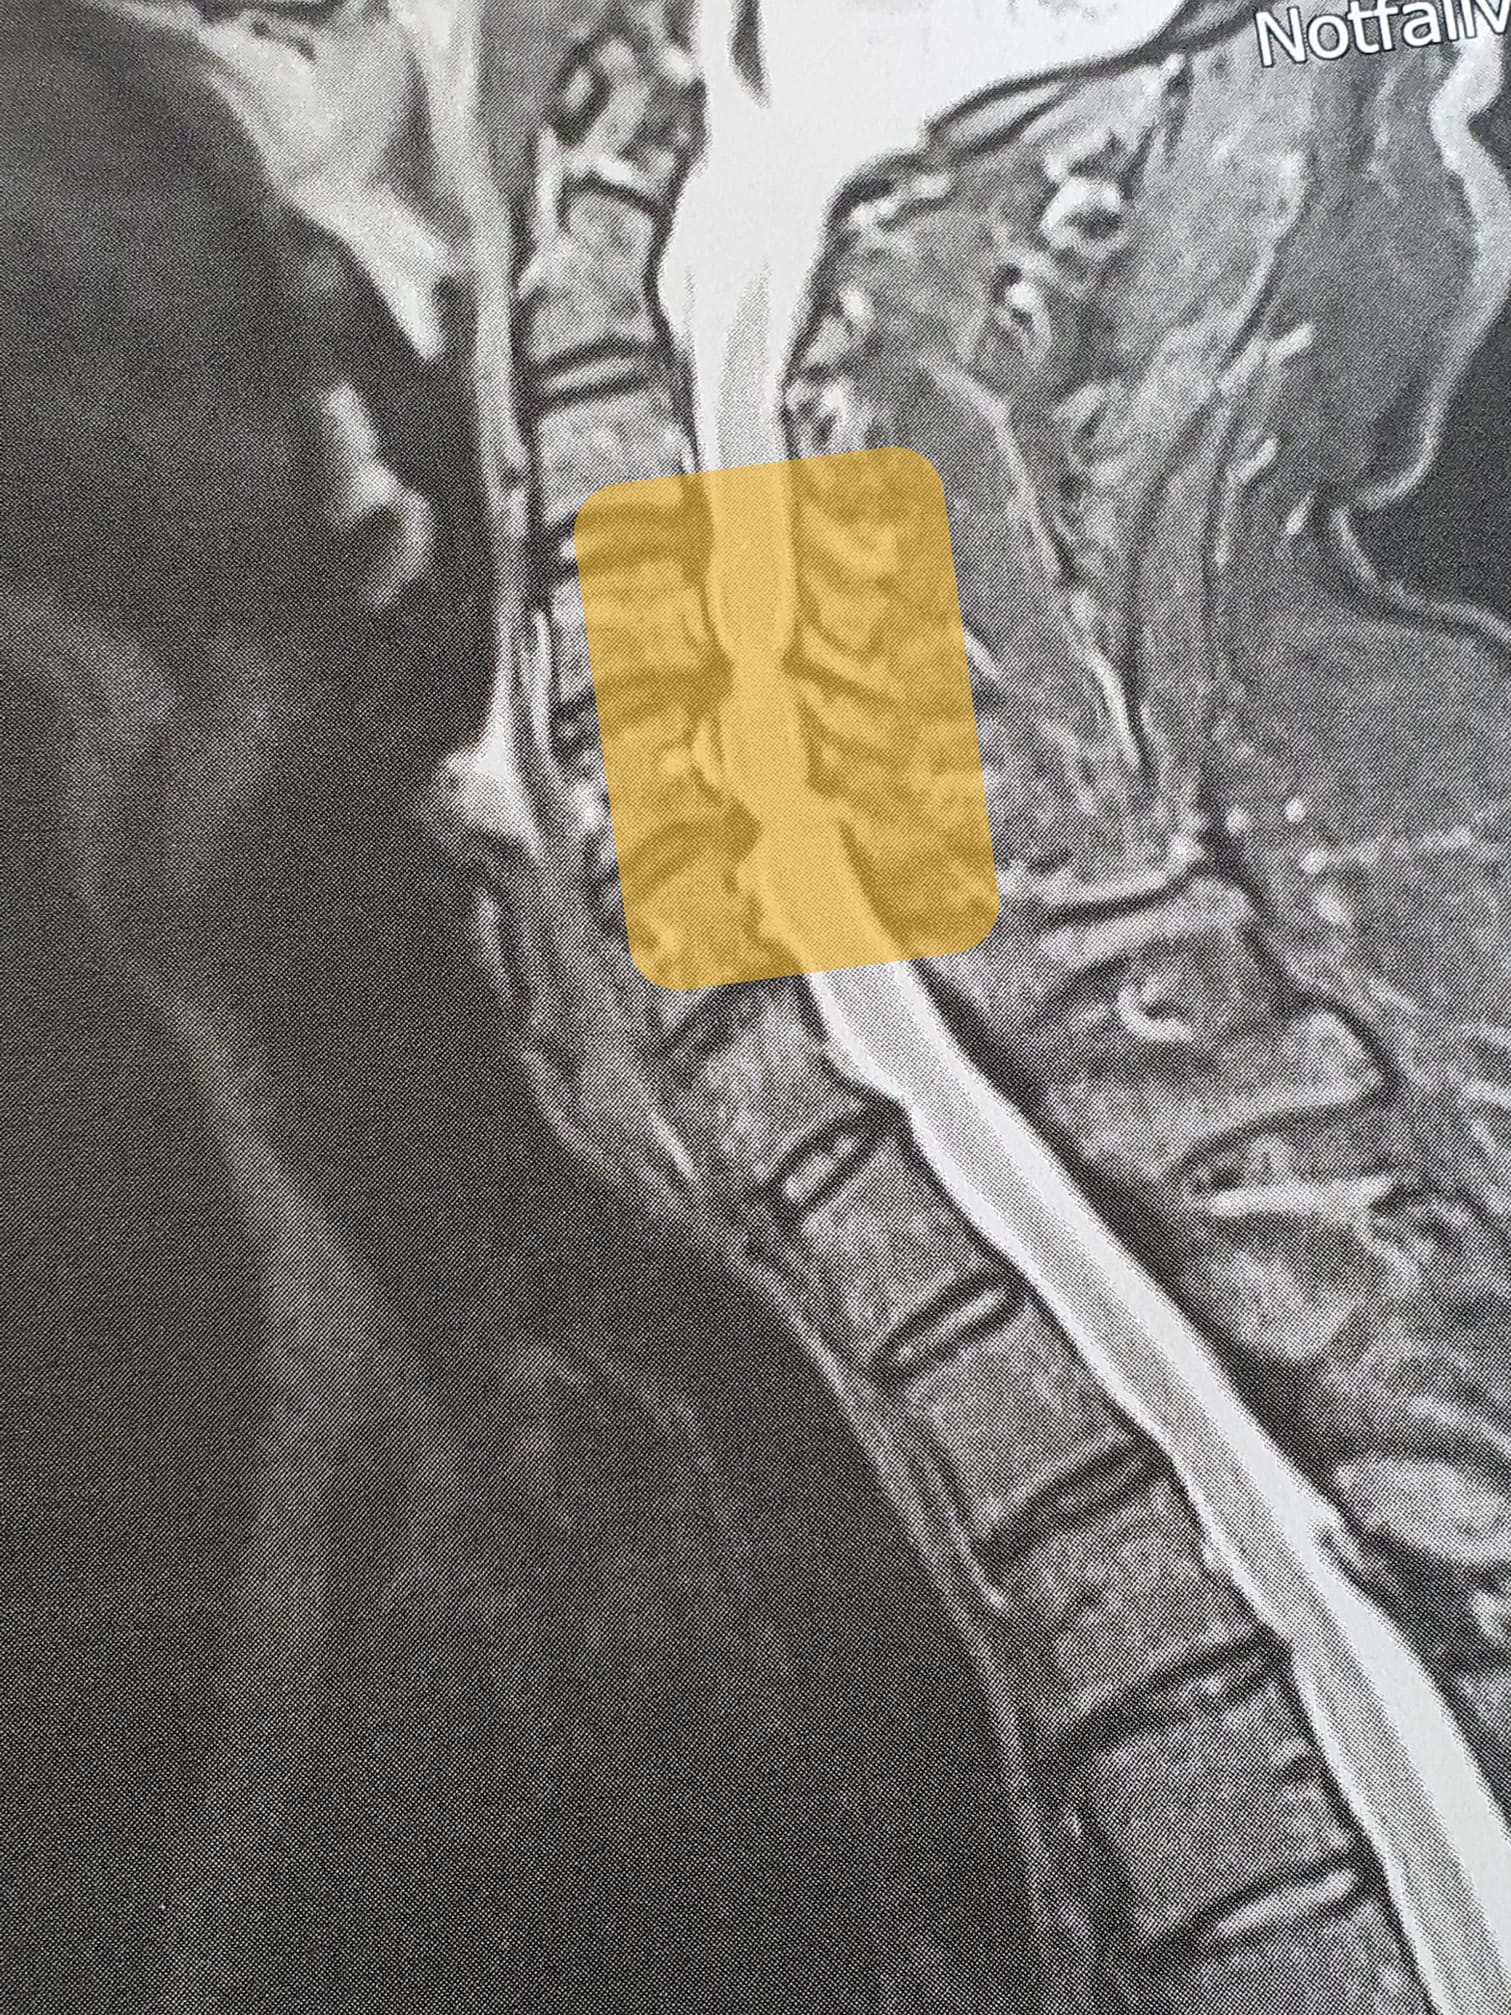

Die zweite Hälfte des Jahres begann am 3. Juni um 15:30 Uhr, als ich mit dem Fahrrad die Bordsteinkante hochfahren wollte, stürzte und meine Halswirbelsäule verletzte. An der Unfallstelle sind beide Arme und das rechte Bein gelähmt. Letzteres zuckt dafür unkontrolliert. Es folgt eine Episode aus Grey’s Anatomie: Ich sah Decken von Krankenhausfluren vorbeiziehen, meine Kleidung wurde zerschnitten und ein Dutzend Ärzte untersuchte mich. Die erste Nacht auf der Überwachungsstation konnte ich an meiner rechten Hand den kleinen Finger strecken. Die anderen Finger waren so kraftlos, dass nicht einmal der Touchscreen meines Handys reagierte. Den rechten Arm konnte ich über den Kopf heben, aber nicht wieder senken: Dann fiel er mir aufs Gesicht.

Es begann ein Weg, der leider und hoffentlich noch nicht zuende ist und der zunächst 2½ Monate durch drei Kliniken führte. Die Bandscheiben C4/5 und C5/6 wurden am 12. Juni in einer fünfstündigen OP entfernt. Ich mache erste Schritte mit einer Gehbank, laufe mit Rollator, lerne, mit Krücken und schließlich frei zu gehen. Für die rechte Hand ist die Butter zum Frühstück anfangs zu hart und das Messer kann ich nur mit einer Griffverdickung halten. Selbst eine halbe Stunde im Rollstuhl sitzen, strengte mich an und ich wurde kaltschweißig. Mittlerweile ist die rechte Hand zwar langsamer als ihre Schwester, aber ich kann wieder tippen, greifen und Teig kneten und meine Kondition reicht für die täglichen Aufgaben.